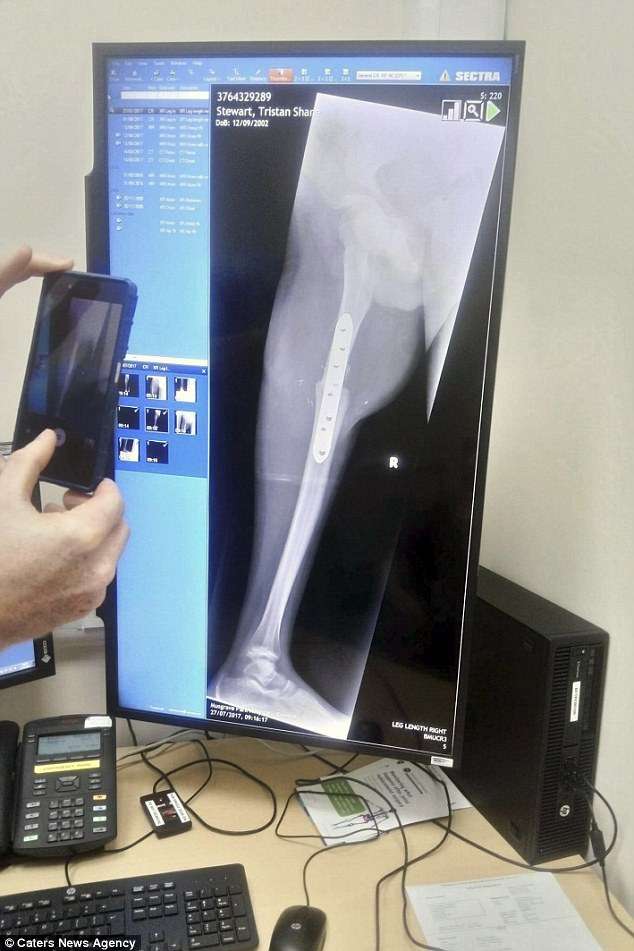

▼2016年3月,爸爸不放心,又帶Tristin去醫院看診,這才知道他罹患了惡性滑膜瘤。Tristin想要保住命,只能接受手術。醫生提出了2個手術方案,一是直接從右腿膝處蓋附近截肢,再裝上義肢,可是沒有了關節,以後會行動不便;二是將截肢的右腳旋轉180度重新接回,可以用腳踝關節代替原本膝蓋的功用,康復之後還能慢跑,就是看起來怪怪的。